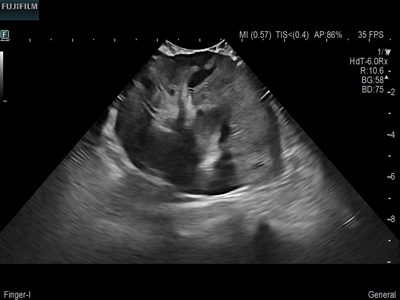

Liver Surgery Procedure using C22I

Curved array deep penetration “I” style finger-grip transducer for open kidney surgical procedures. Allows for palpating organs and scanning at the same time.